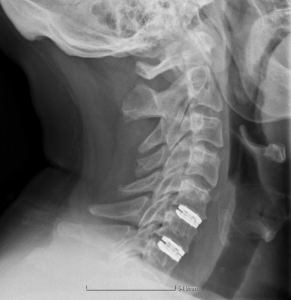

Δισκοπλαστική αυχένος σε δύο επίπεδα

Χρησιμοποιώντας καθοδήγηση ακτίνων Χ (C-Arm), εισάγεται ο τεχνητός δίσκος στον χώρο που καταλάμβανε προηγουμένως ο φυσικός δίσκος.